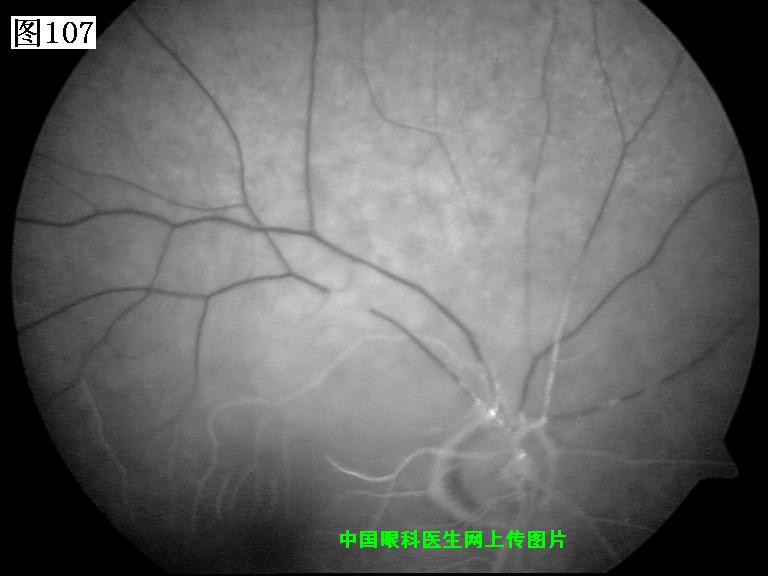

105 106 107 108